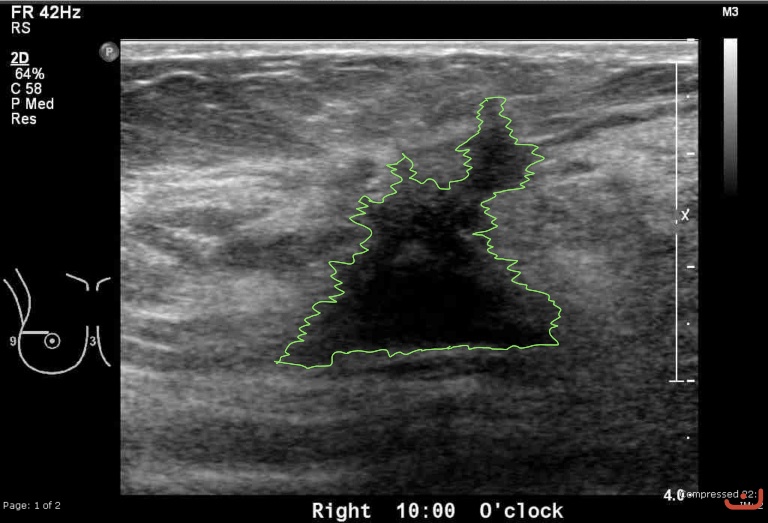

Case 23-G1

Malignant solid mass

Friday, 22 May 2015

214.14 KB (768 x 523 px)